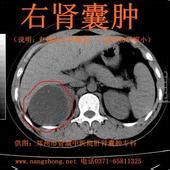

右腎囊腫右腎囊腫2-3cm,沒有症狀不需要治療;右腎囊腫穿刺治療後復發,有沒有別的治療方法;右腎囊腫會不會影響腎功能等問題上。右腎囊腫自然變化緩慢,主要是數目的增加,其次是大小的輕度增加,少數輕度縮小。右腎囊腫一般會出現腰疼、腰困、高血壓等症狀,可以出現血尿和局部疼痛,也可出現腎盞梗阻和繼發感染,但不會導致腎功能衰竭。

一般而言,右腎囊腫接近或超過5CM就應積極治療,否則長期壓迫腎實質,就會造成腎單位缺血缺氧,出現高血壓,導致大量蛋白漏出。傳統治療方法常採用去頂減壓術和穿刺硬化術,但囊腫減小後,在壓力作用下往往會迅速長大,常會復發,利少弊多。除以上二項外,合理飲食,少吃刺激性食物;安排好工作和休息,不能太累也是右腎囊腫患者切實應該注意的問題,累及損身是右腎囊腫患者應該遵循的原則。